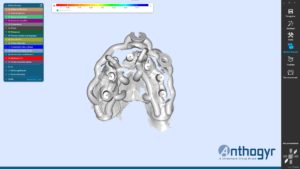

La planification implantaire a été réalisée sur le logiciel SMOP. Les empreintes ont été superposées avec le cone beam du patient.

Les implants ont été posés virtuellement, ce qui a permis au praticien d’évaluer la possibilité d’extraire, implanter et mettre en charge immédiatement lors d’une même séance.

Une fois la planification validée, un guide implantaire SMOP a été dessiné et imprimé (imprimante STRATASYS poly-jet avec précision à 16 microns ).